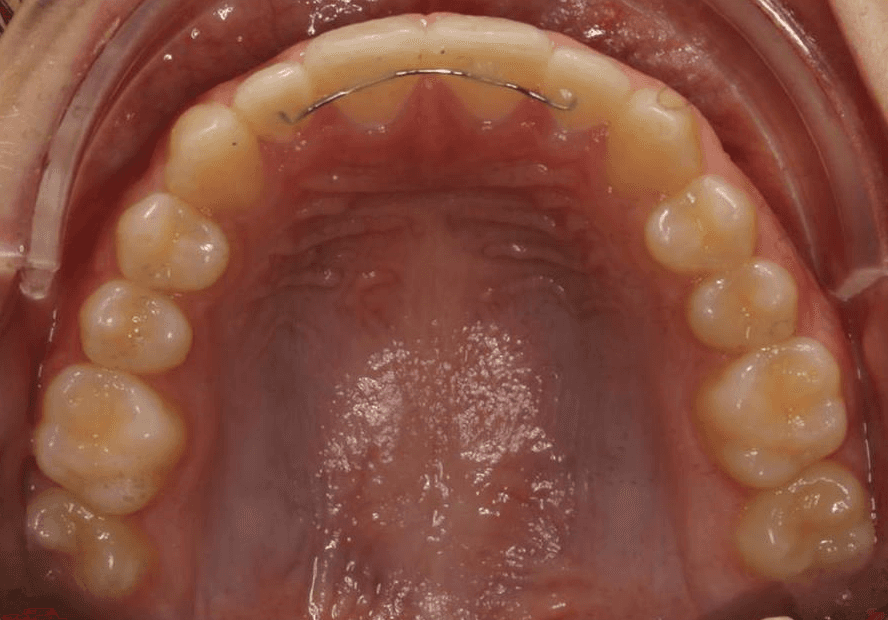

Female, 14 | Treatment time: 21 months

Diganosis: Lower anterior crowding, mild maxillary spacing, misalignment of anterior teeth, rotated premolars and molars

Initial treatment

INTRAORAL